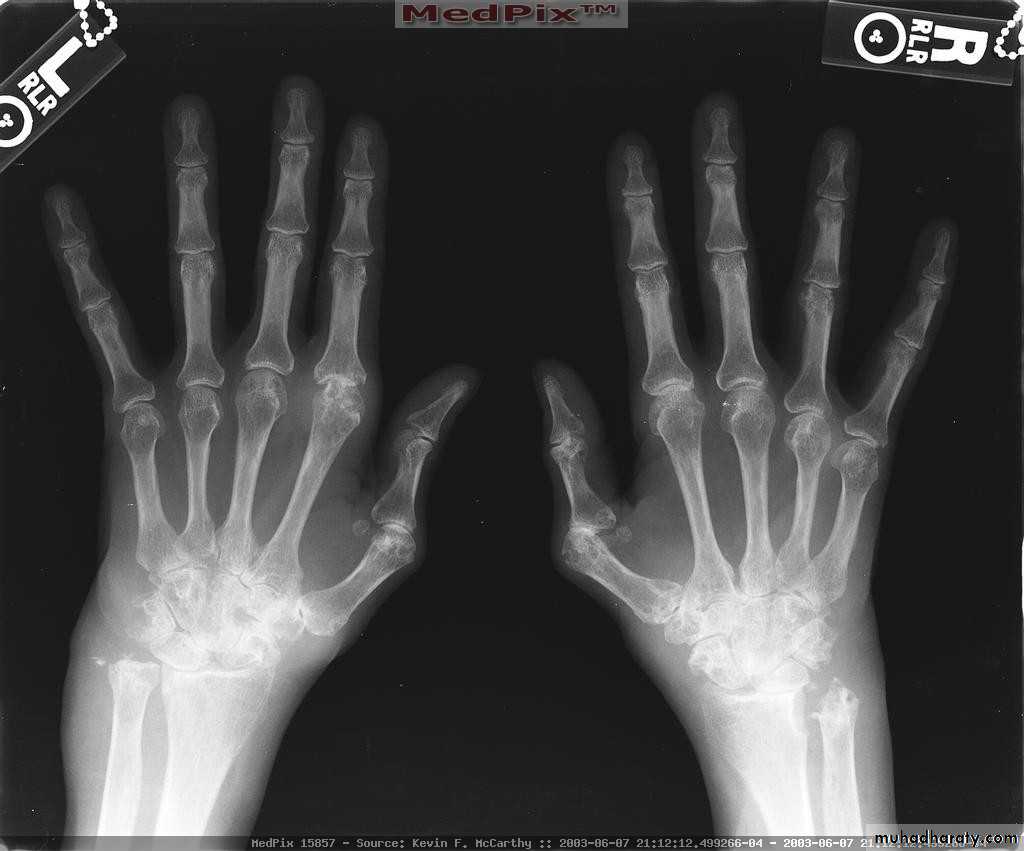

Severe erosive changes at radio-ulnar joints carpal bones at the metacarpal heads

Bilaterally symmetricSevere ulnar deviation

Severe erosions of MCPsComplete destruction of the wrist

Resorption of the carpals and the heads of the metacarpals

Radial deviation of the wrist